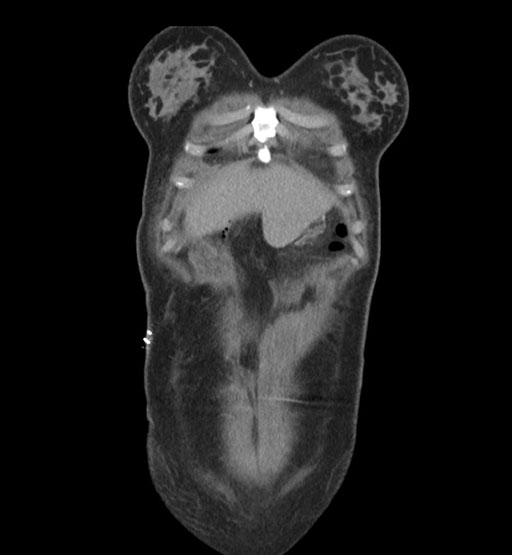

Imaging Analysis

Look through the patient's CT scan to identify any areas of concern for the necessary procedure.

Coronal Arterial

Coronal Venous

Based on initial findings, which issue(s) would you be most concerned about?